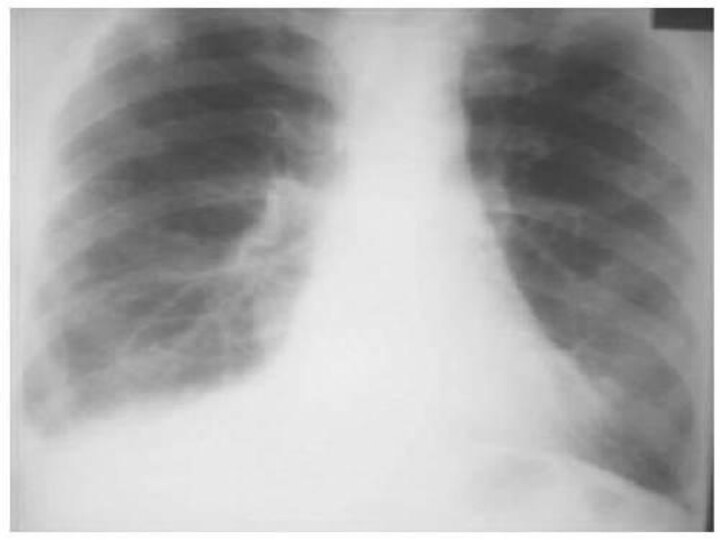

Дифференциальная диагностика заболеваний плевры

Раздел: Фотоэссе